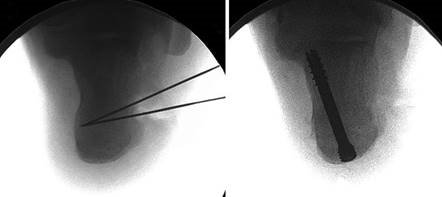

The Lapidus Arthrodesis (First TMT Fusion)

For severe deformities or hypermobility, the Lapidus procedure provides robust stabilization of the medial column. A dorsal or medial incision is utilized over the first TMT joint. The extensor hallucis longus (EHL) is retracted dorsally, and the tibialis anterior tendon is identified and protected at its insertion on the medial cuneiform and first metatarsal base. The TMT joint capsule is incised, and the joint is thoroughly debrided of all articular cartilage using a combination of osteotomes, curettes, and a high-speed burr.

To achieve multiplanar correction, the surgeon must address the sagittal, coronal, and transverse planes. The first metatarsal is plantarflexed to restore the longitudinal arch, rotated out of pronation to realign the sesamoids, and translated laterally to close the IMA. Subchondral drilling or feathering is performed to optimize the biological environment for fusion. Fixation is traditionally achieved with two or three crossed solid or cannulated screws (typically 3.5mm or 4.0mm). Recently, plantar or medial locking plates have gained immense popularity due to their superior biomechanical construct, allowing for earlier weight-bearing. Bone graft or orthobiologics may be packed into the arthrodesis site to stimulate osteogenesis.

Image

Digital Templating and Patient Positioning

Digital templating software is employed to determine the center of rotation of angulation (CORA) and to simulate the proposed osteotomy or fusion. This allows the surgeon to anticipate the degree of translation required, the potential for metatarsal shortening, and the appropriate size of fixation hardware. For a Lapidus procedure, templating helps calculate the exact wedge of bone to be resected from the medial cuneiform and first metatarsal base to achieve the desired multiplanar correction.